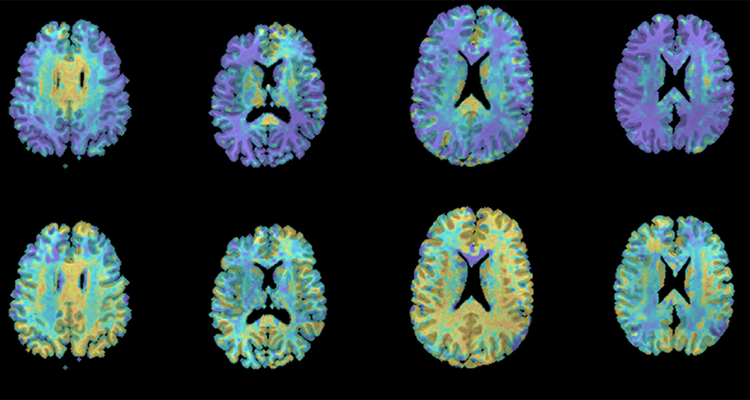

Une étude comportementale, menée par une équipe de NeuroSpin, a évalué le traitement cérébral de la durée par la mémoire de travail en faisant mémoriser à des participants une séquence d’intervalles de temps et en leur faisant ensuite reproduire la durée de chaque intervalle. Les résultats suggèrent que le cerveau traite la durée de chaque événement comme une information distincte.